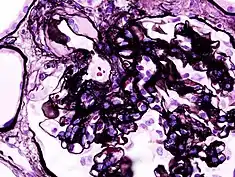

_HE.jpg.webp)

_PAM.jpg.webp)